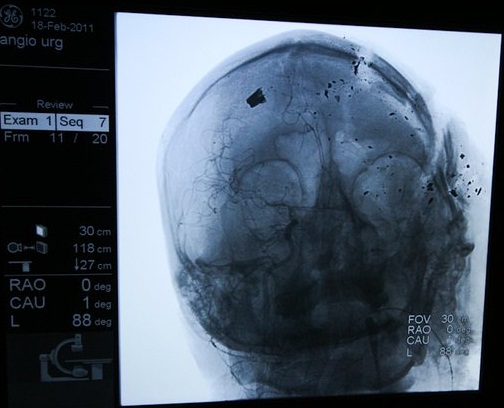

The most difficult case was that of Mr. Abulredha Buhmaiyed (32 years). A bullet penetrated his head. The consultant Dr. Nabeel Hameed tried to rescue him. A surgical operation continued for three hours, but failed to extract the bullet from his skull. The consultant Dr. Nehad AlShirawi worked to follow-up his case. Abulredha remained clinically dead for two days. He passed away on February 21. Before that Dr. AlShirawi collapsed in a fit of weeping in front of the cameras. Later she would pay the price of that weeping in the martial tribunal.

The female consultant Dr. Badria Toorani treated a case where a bullet had been lodged at the top of the thigh and close to the pelvis. Dr. Basem Mirza assisted her. They x-rayed the bullet. A group of journalists reached the hospital. They asked to see the cases in the recovery room. Dr. Basem Dhaif showed them the x-ray that displayed the bullet that had been extracted. But he said: “It was not me who treated this case”. The journalists asked for the bullet to photograph. They were told that it had been put in a bag and was secured. But where had it gone? One said “It was put in a bag and given to the human rights organization”